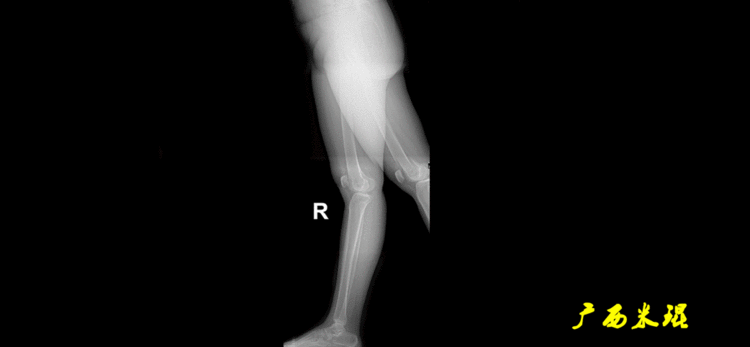

站立侧位(矢状面)股骨头中心与踝关节中心的连线也通过膝关节中心,这也是下肢的机械轴线,这也是下肢力线。

矢状面的下肢力线常常被医生忽视,其实它的改变也是膝关节疼痛的常见原因。